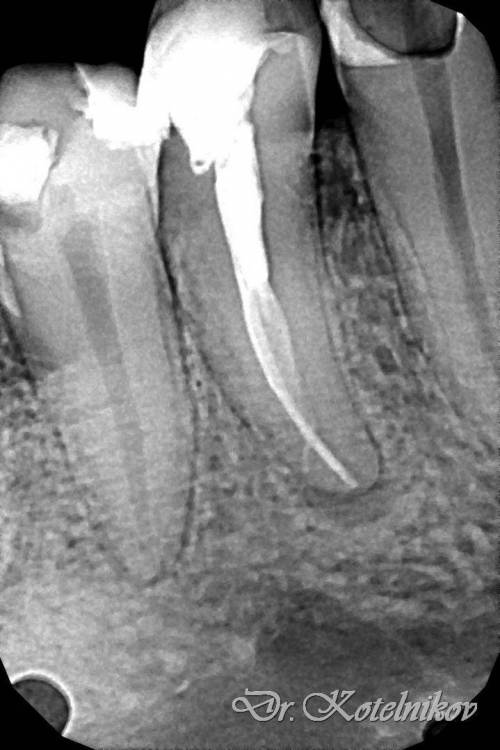

Ico Опубликовано 10 апреля, 2022 Автор Поделиться Опубликовано 10 апреля, 2022 (изменено) 3 отдельных канала в нижнем премоляре,паковка похожая как у Томаса Ланга.Каллибровка,паковка апексов была по S2 протейперу + 25 к. Изменено 10 апреля, 2022 пользователем Ico 1 1 2 Ссылка на комментарий